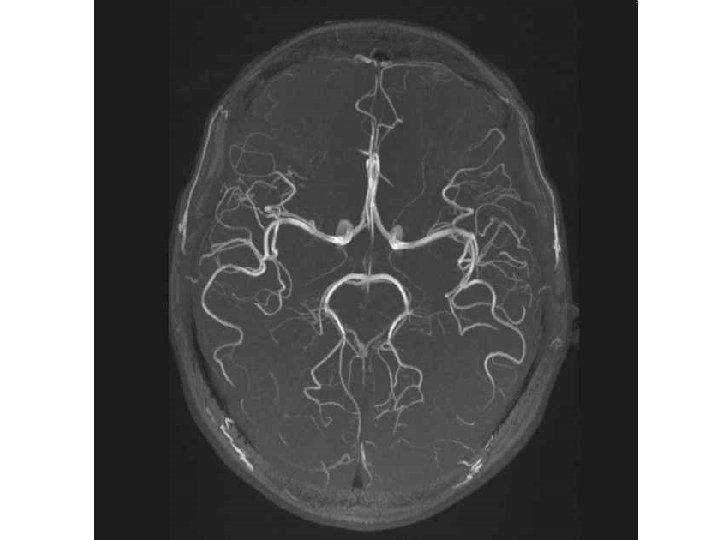

A. carotis interna – pars cerebralis • • a. ophthalmica a. hypophysialis superior a. communicans posterior a. choroidea anterior terminal branches: • a. cerebri anterior • a. cerebri media circulus arteriosus cerebri Willisi

Patrs of aa. cerebri • a. cerebri ant. – pars precommunicalis; segmentum A 1 – pars postcommunicalis; segmentum A 2 • a. cerebri media – pars sphenoidealis/horizontalis; segmentum M 1 – pars insularis; segmentum M 2 • a. cerebri post. – pars precommunicalis; segmentum P 1 – pars postcommunicalis; segmentum P 2